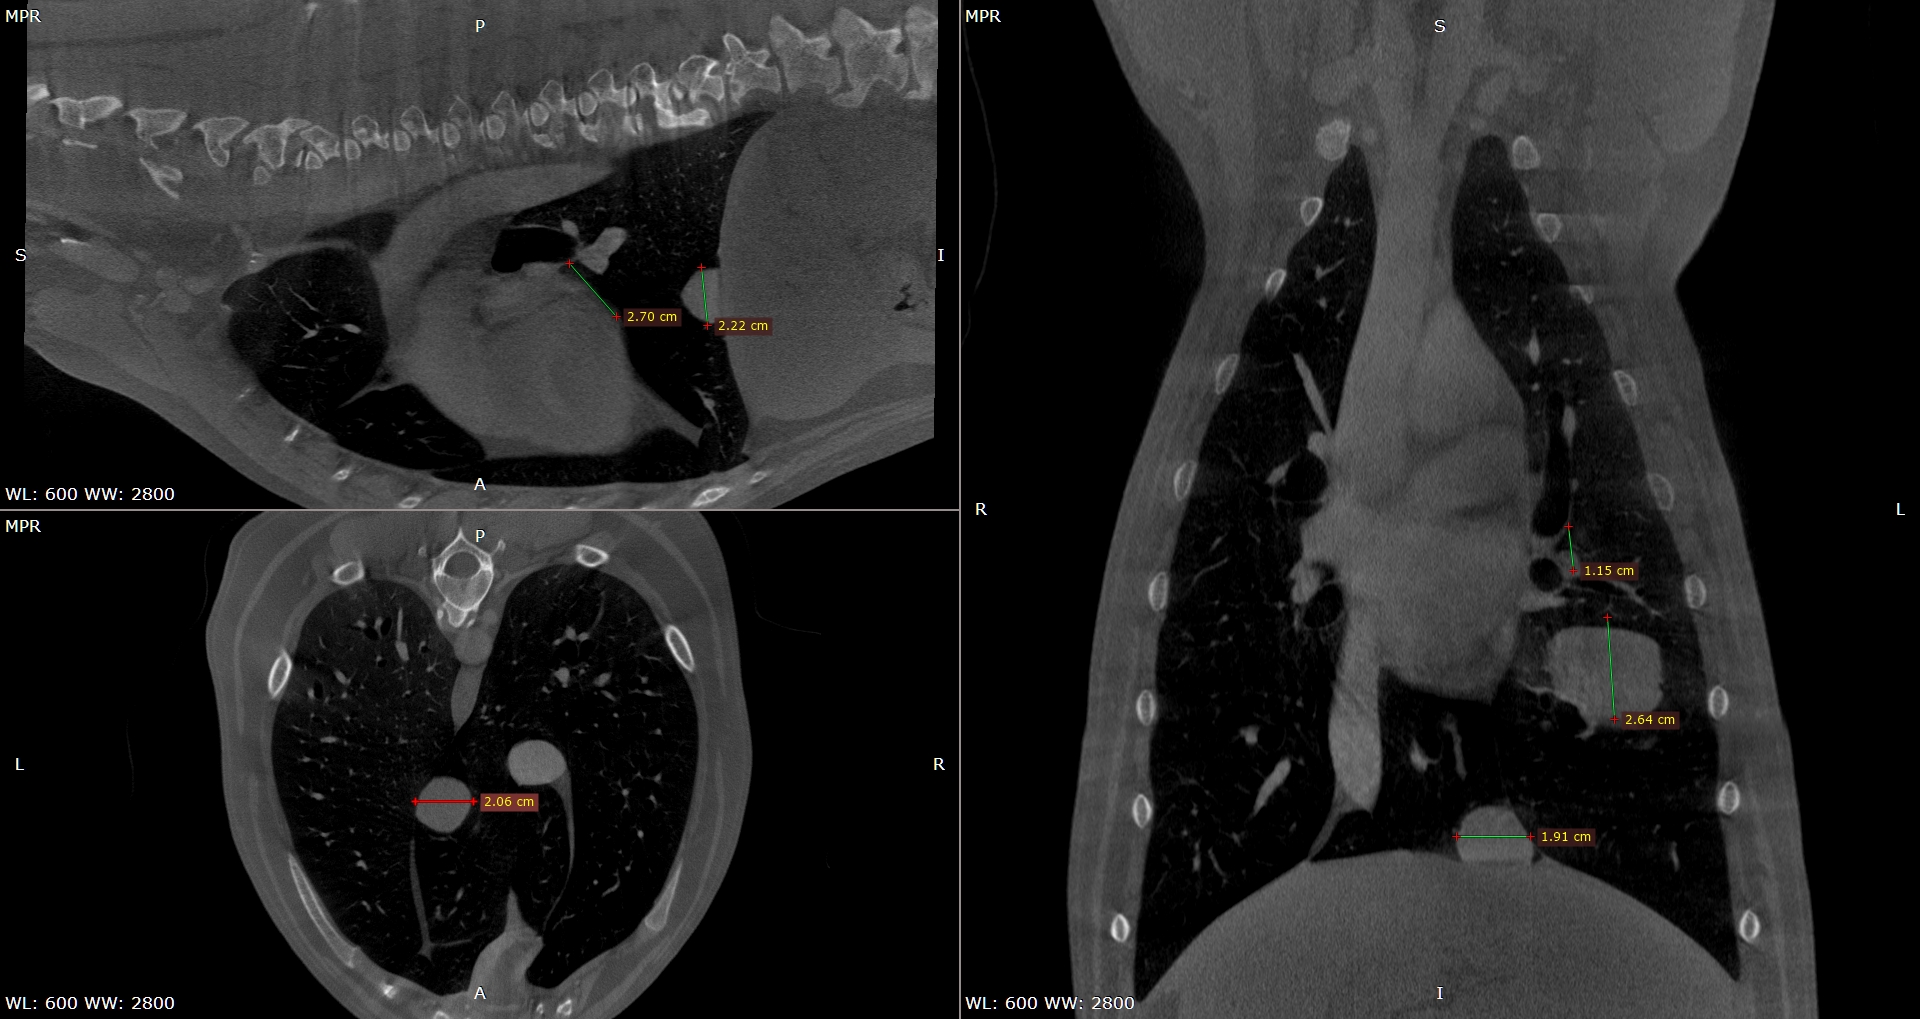

Lungen CT und Volumentomografie der Lunge beim Hund beim unklaren From www.tierarzt-sommer.de

Lungen CT und Volumentomografie der Lunge beim Hund beim unklaren